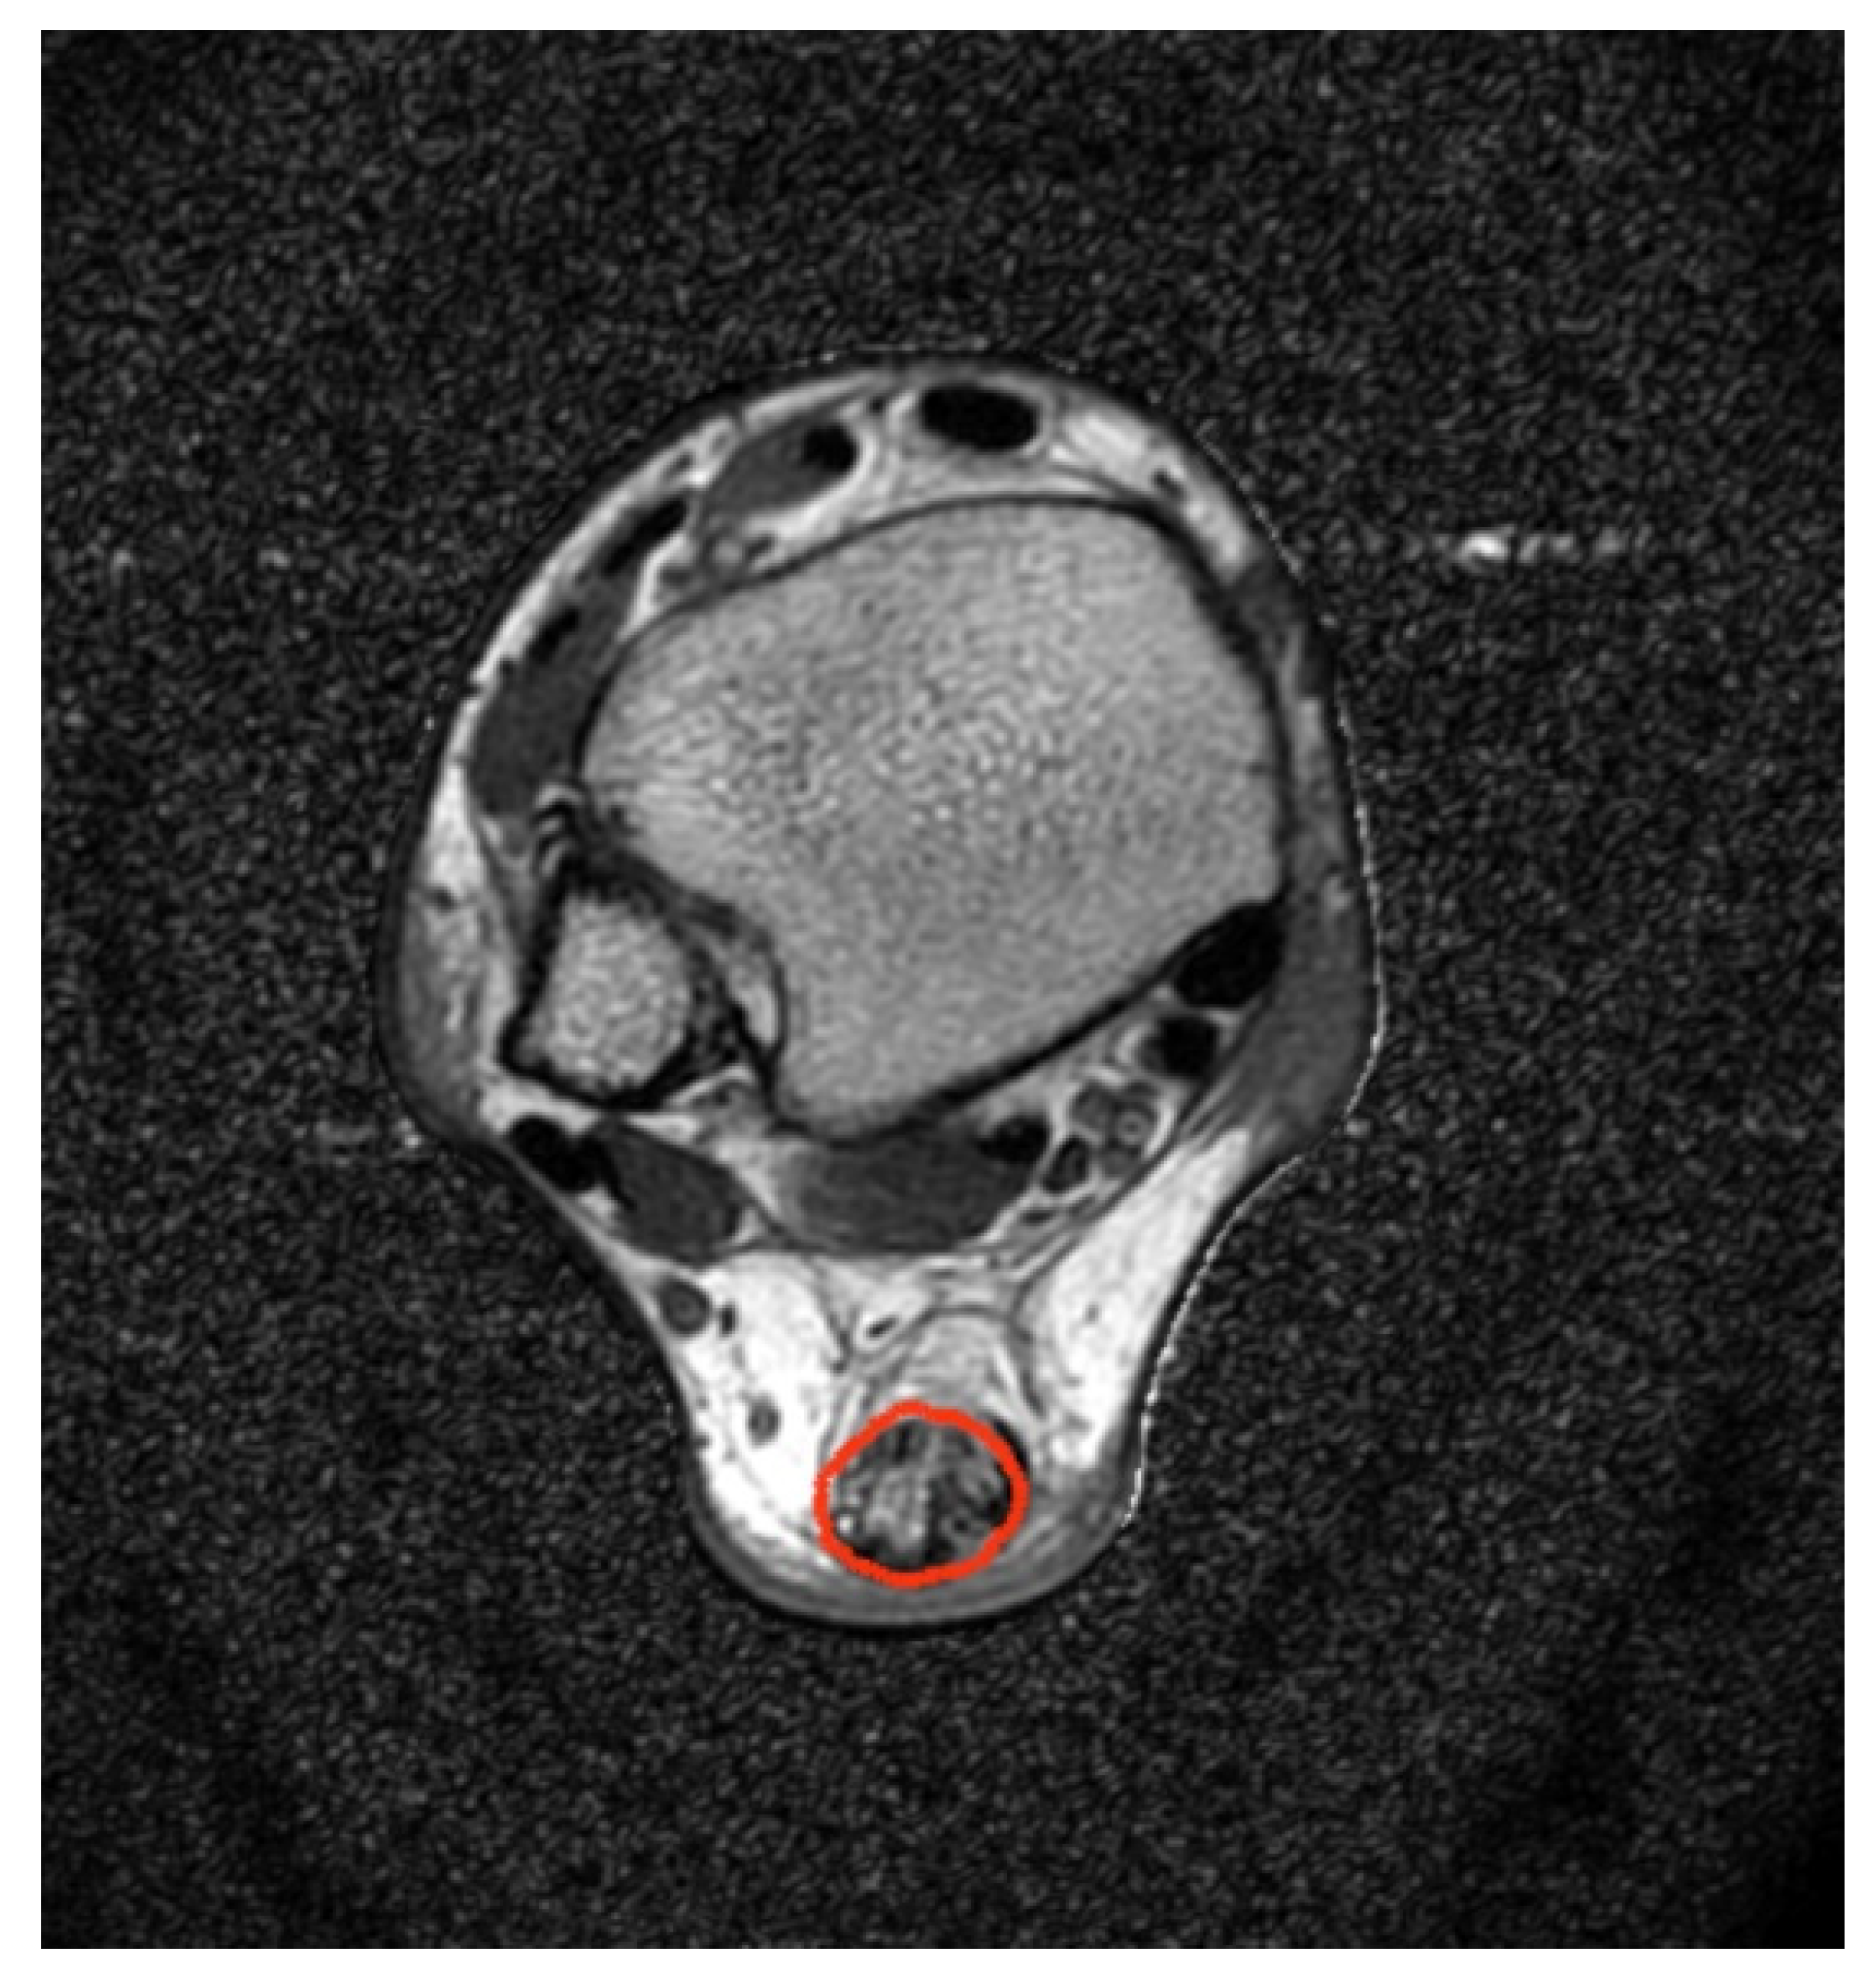

- Regulski, P.A.; Zielinski, J. Multi-step segmentation algorithm for quantitative magnetic resonance imaging T2 mapping of ruptured Achilles tendons. IEEE Access 2020, 8, 199995–200004. [Google Scholar] [CrossRef]